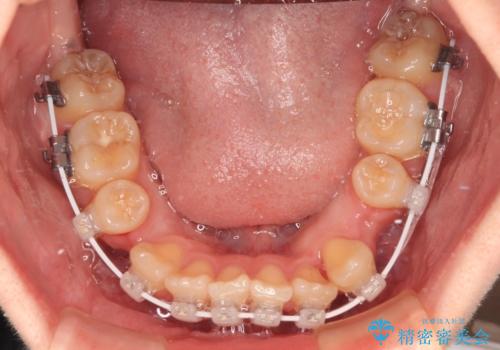

- 矯正装置

- 審美装置

口元の突出感はなかったものの、捻転や八重歯を改善するために補助装置を併用する必要がありました。

予定の2年半を越えてしまいましたが、無事にきれいな口元に仕上げることができました。